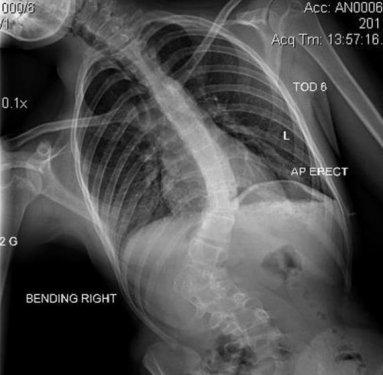

Manken Zoe Blenkinsop dünyaya skolyoz rahatsızlığıyla geldi. Sırtındaki omuru S şeklinde eğri olan genç kız, uzun süre ayağa kalkmakta bile zorlandı.Her seferinde büyük acılar çeken genç kızın sırtında bir yumru oluştu.

11 yaşında teşhis konulan kıza operasyon yapılabilmesi için kemiklerinin yerleşmesi gerektiği söylendi.

Bunun için de 18 yaşına kadar beklemesi gerektiği anlatıldı.